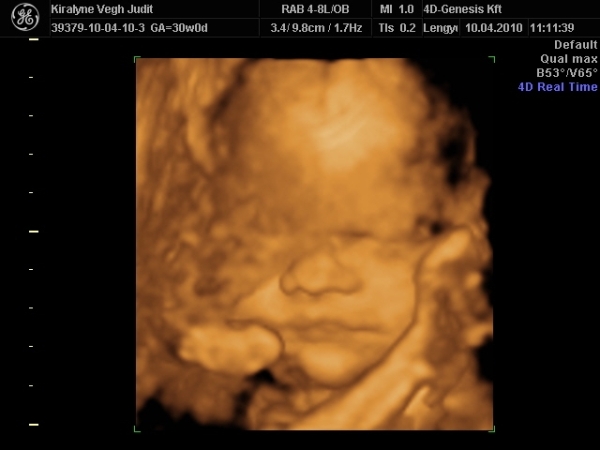

4D-re holnap megyünk 11-re, utána meg tervezünk egy kis csavargást. :lol: :lol: :lol:

Ma jól elfáradtam. Voltunk 4D-n, a várban és a Csodák palotájában. Rengeteget sétáltunk, nem érzem a lábamat.

A lényeg, hogy Izi baba nagyon jól van,

Babócám fejjel lefele, idézem: "méhlepény olyan távol van a méhszájtól, mint Makó Jeruzsálemtől." :oops: :oops: :oops:

Szóval nem értem a szerdai uh-ot. :oops: :oops:

"0" fokban érett a lepény, 1741g kis csöppségem, combcsont mérete alapján már 32 hetesnek felel meg. Amúgy minden mérete alapján 1 héttel idősebb. Magzatvíz átlagos. És tiszta apja. :lol: :lol: :lol: :lol:

És a képek.